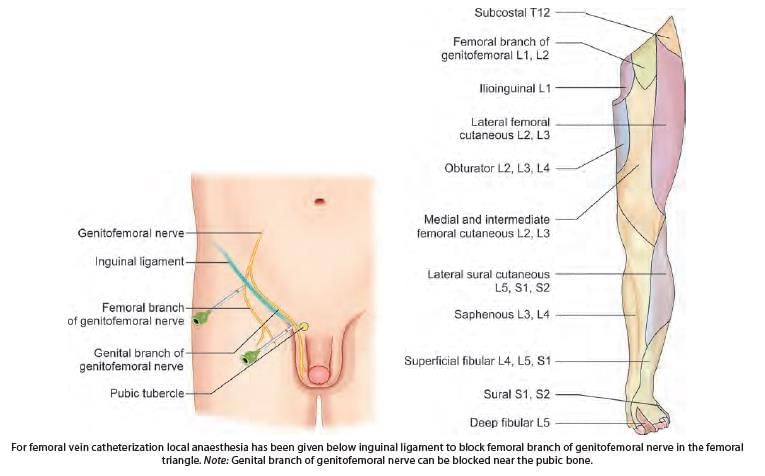

For femoral vein catheterization local anaesthesia has been given below inguinal ligament. Which of the following nerve is blocked?